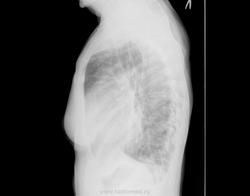

Вводные данные: 47 лет, жалобы на одышку, боли за грудиной. терапевт направил на рентгенографию грудной клетки

Какое заключение по этим снимкам вы бы сделали, коллеги?

Ассиметрия грудной клетки, S-образная деформация хребта: шейно-грудной сколиоз (вершина искривления на уровне Th5 - Th6), угол сколиоза 26о и грудопоясничный сколиоз (вершина искривления на уровне Th11), угол сколиоза 17о. Легочные поля сниженной прозрачности, усилен легочной рисунок. Сердце увеличено за счет ПЖ и ЛЖ талия, сердца сглажена, КТИ=0,6

Сколиоз ІІІ степени. Пневмофиброз. Хроническое легочное сердце.

Вероятен дефект межпредсердной перегородки, диффузное снижение тонуса миокаарда, венозный застой в малом круге 1 ст. Правосторонний, с вершиной на Th 5 сколиоз 2-3 ст. Справа внизу несколько тонкостенных ячеистых структур - порок развития бронхов.

Не думаю, что сколиоз мог вызвать такие проблемы с легкими. Все таки точно определить степень сколиотической деформации на данном снимке затруднительно.